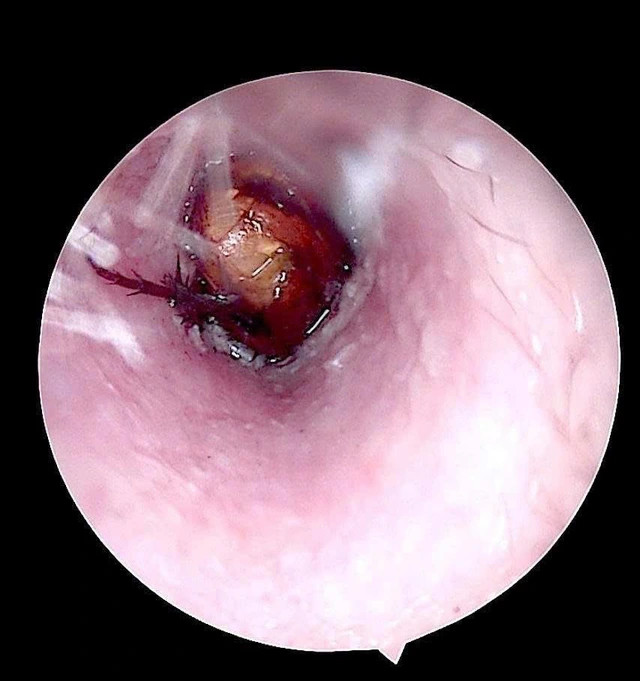

Côn trùng sống trong ống tai của bệnh nhân.

Qua kiểm tra, bác sĩ ghi nhận ống tai ngoài bên phải của bệnh nhân có hiện tượng xung huyết, có dị vật sống. Các bác sĩ đã tiến hành nội soi, gắp dị vật là một con côn trùng có kích thước khoảng 1,5cm.

Kiểm tra sau lấy dị vật, phát hiện màng nhĩ bệnh nhân nề đỏ do phản ứng viêm và kích thích trong quá trình tự lấy dị vật.